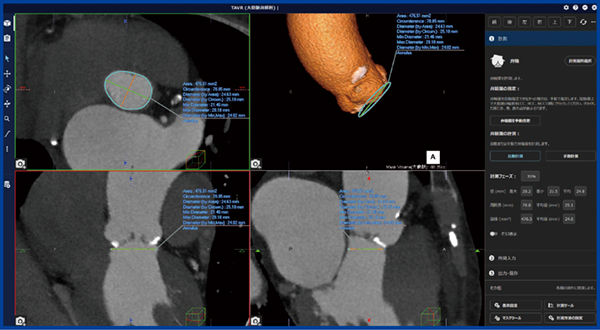

REVORAS の「TAVR大動脈弁解析」(図2)は,弁輪面やLVOTなどTAVI弁の種類・サイズ選定に必要な箇所の自動計測機能が搭載されている。計測項目はアイコンで表示され,アイコンをクリックしていくことで必要な箇所の計測を終えることができる。計測項目が多いTAVIのプランニングにおいても,計測が終了した項目にはチェックマークが入り,漏れなく解析を進めることが可能だ。また,画面左側は4分割され,左上から時計回りにMPRのアキシャル(SAX view),volume rendering(VR view),MPRのコロナル(coronal view),サジタル(sagittal view)が表示される(図2)。

図2 REVORAS「TAVR大動脈弁解析」の弁輪面計測~弁輪面の自動認識

左画面は4分割で各viewを表示,右コラムに計測や操作ボタン,解析結果の数値が表示される。